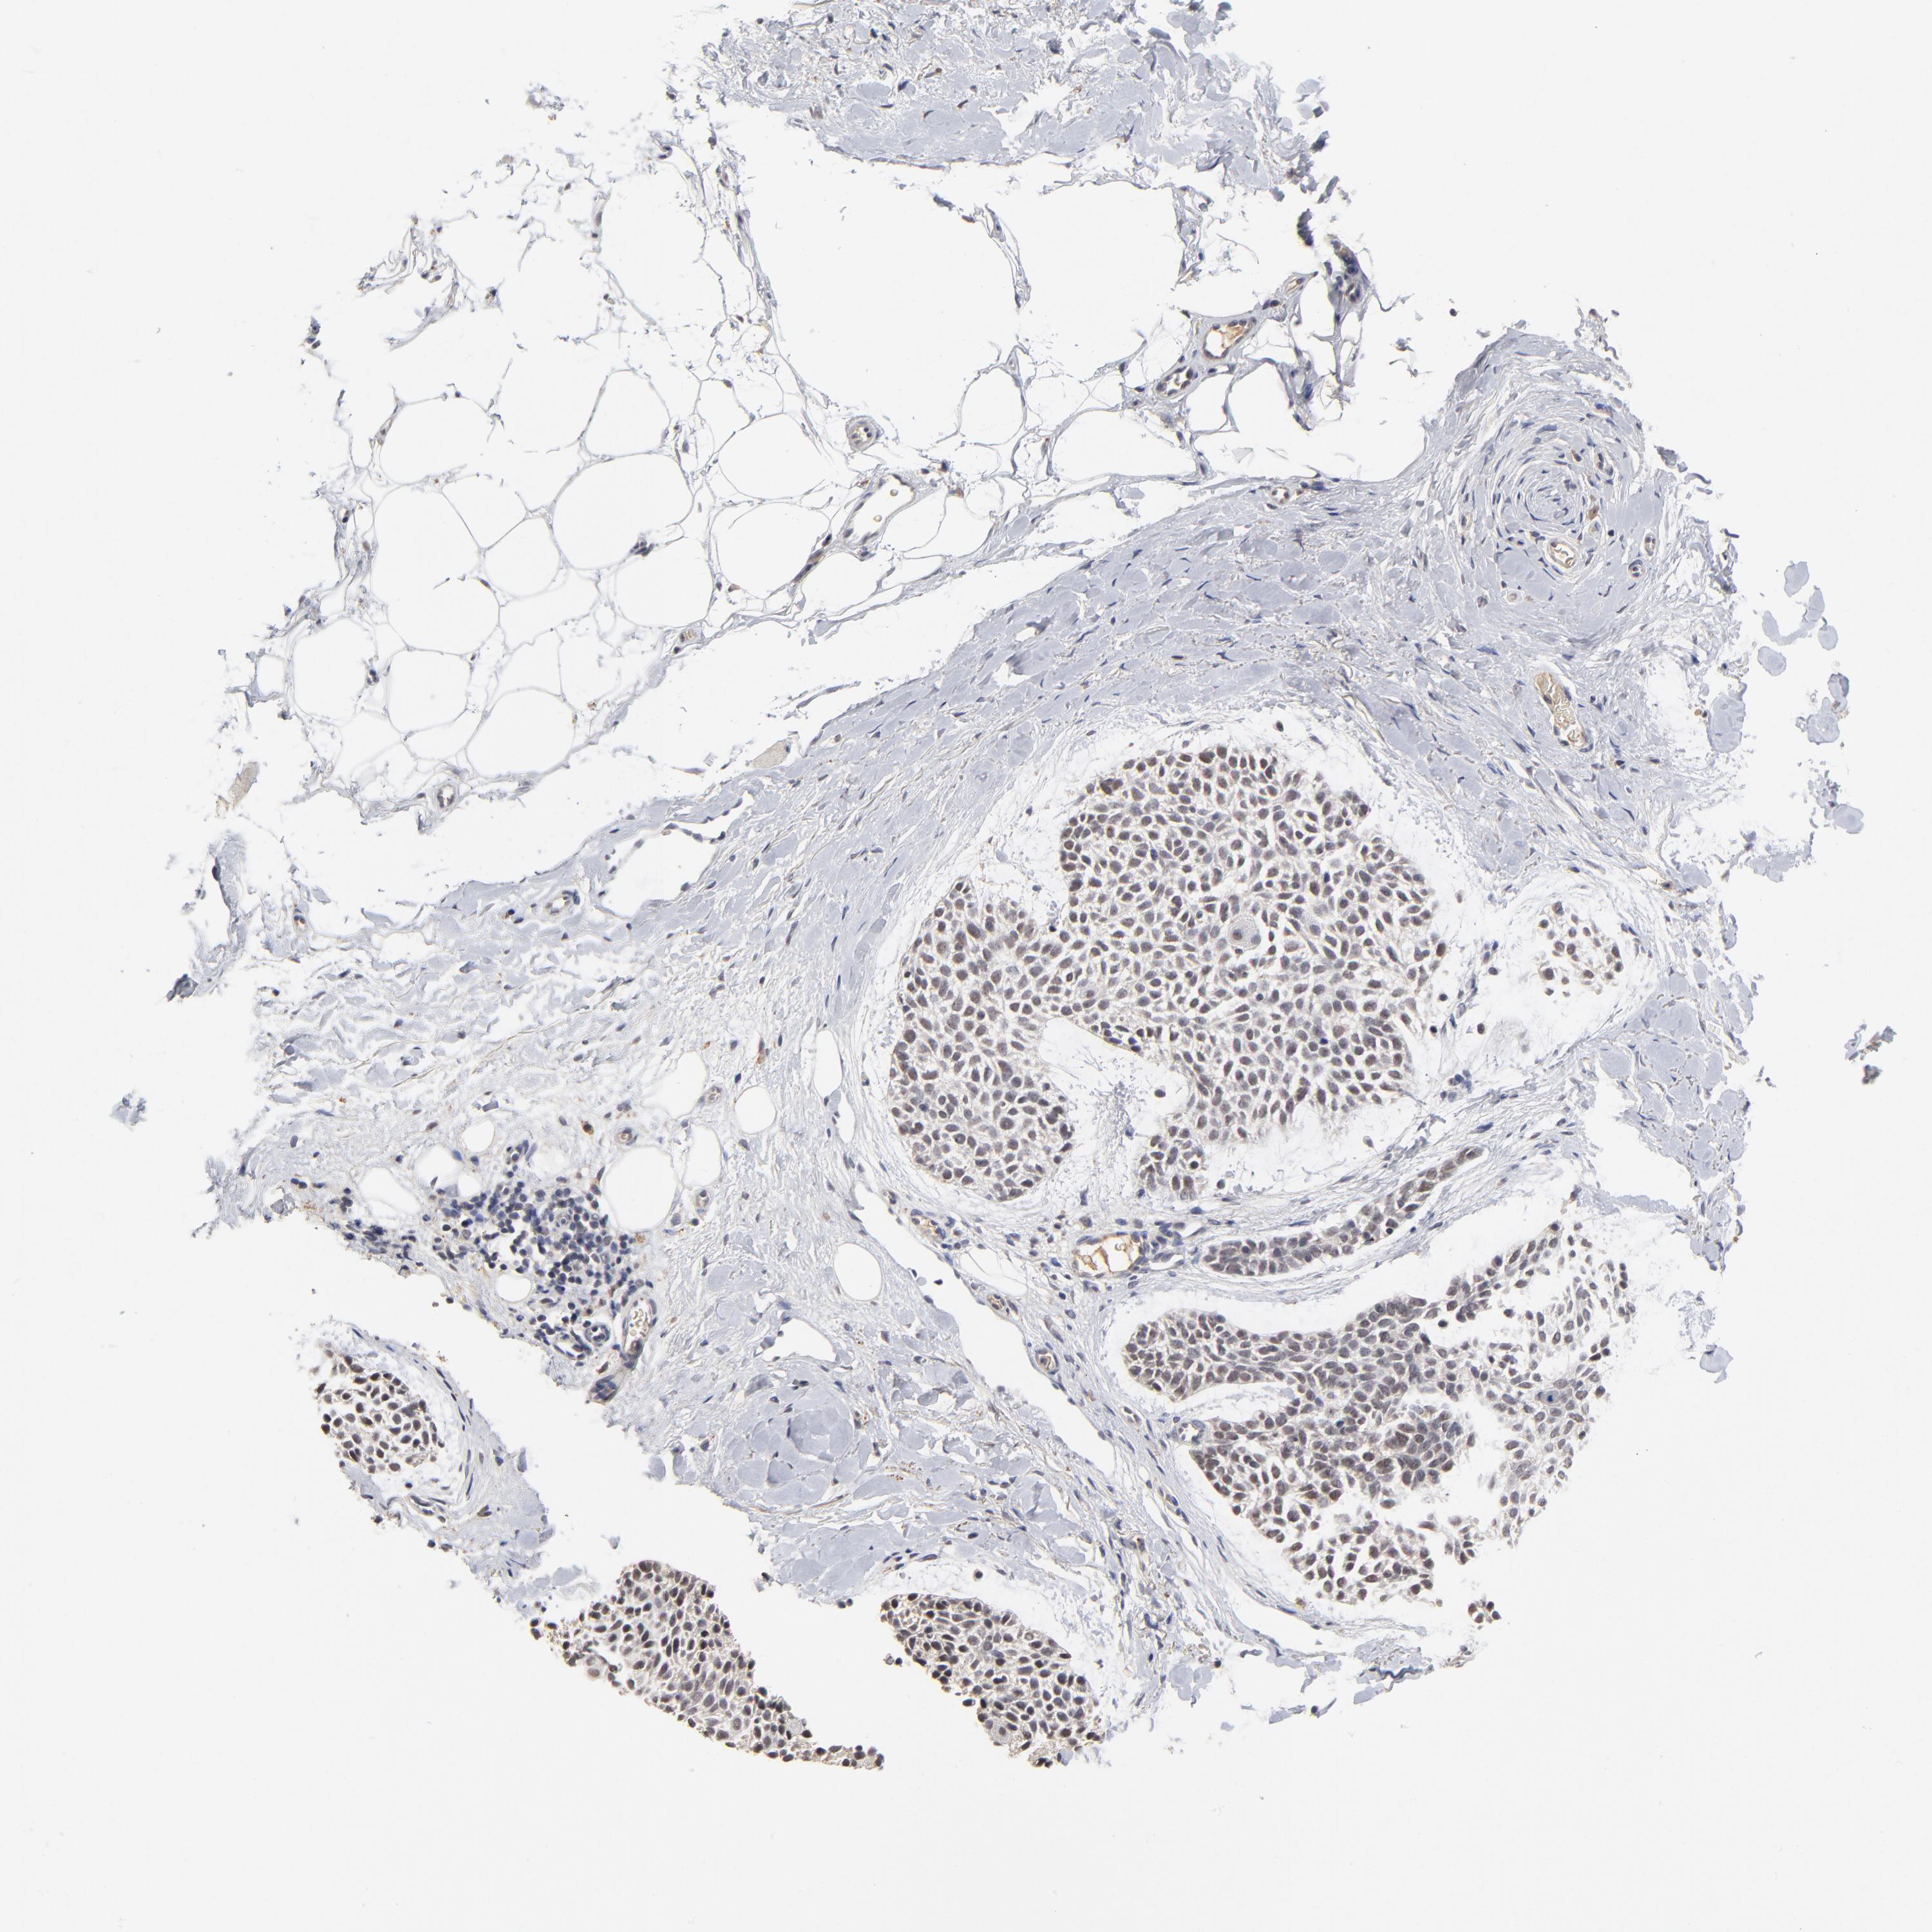

SKIN CANCER - Protein expressioni

A mouse-over function shows sample information and annotation data. Click on an image to view it in a full screen mode. Samples can be filtered based on level of antibody staining by selecting one or several of the following categories: high, medium, low and not detected. The assay and annotation is described here.

Antibody stainingi

Antibody staining in the annotated cell types in the current human tissue is reported as not detected, low, medium, or high, based on conventional immunohistochemistry profiling in selected tissues. This score is based on the combination of the staining intensity and fraction of stained cells.

Each image is clickable and will lead to virtual microscopy that enables deeper exploration of all samples and also displays staining intensity scores, fraction scores and subcellular localization as well as patient and tissue information for each sample.

Antibody HPA003293

Staining

High

Medium

Low

Not detected

Intensity

Strong

Moderate

Weak

Negative

Quantity

>75%

75%-25%

<25%

None

Location

Nuclear

Cytoplasmic/membranous

Cytoplasmic/membranous,nuclear

Squamous cell carcinoma, NOS

Basal cell carcinoma